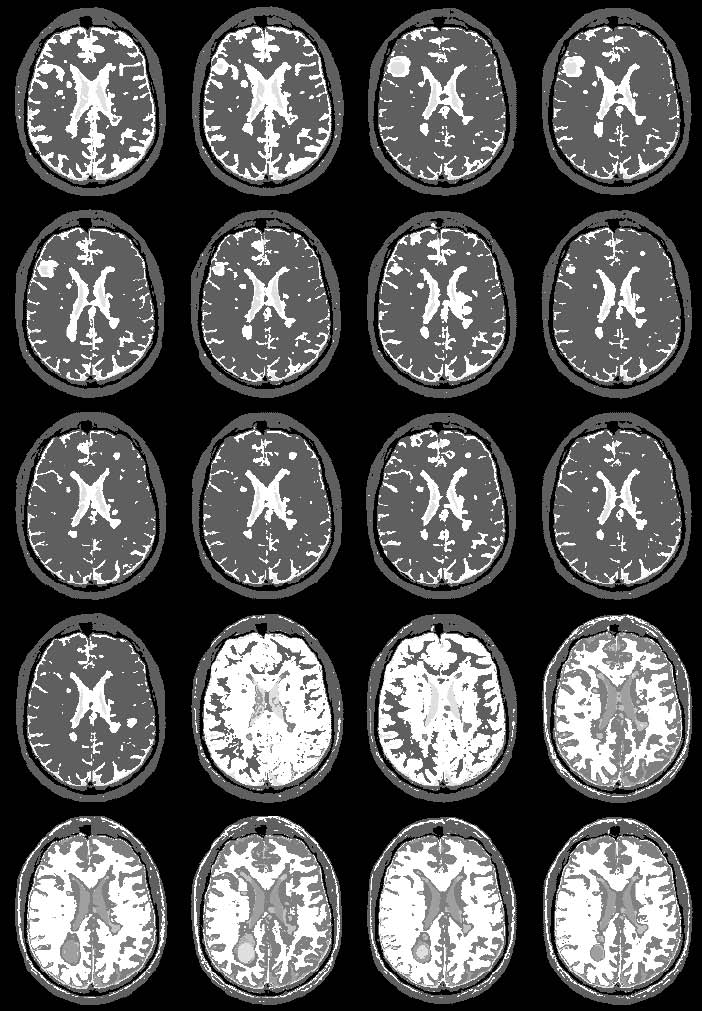

#[[media:seven.jpg|longituidinal MS, one subect, segmentaiton result without EM]]

#[[media:eight.jpg|" " " with EM]]

images:

7. longituidinal MS, one subect, segmentaiton result without EM

8. " " " with EM